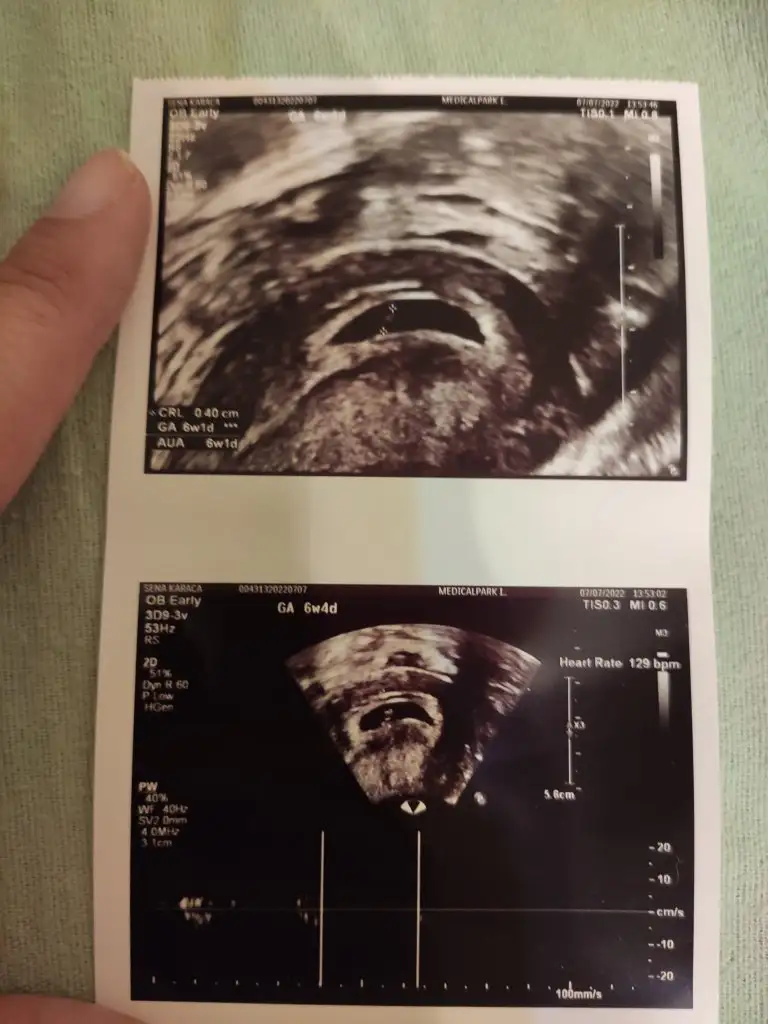

Geçmiş olsun canımcım dikkat et kendine. Kalp atışı olan ultrason görüntüsünde yazıyor yok mu sendeGünaydın canlar , dün gece biraz korkuttu bizim ki beni. Bir kaç damla sadece silince kirmizi kan geldi. Birazda agrim var ama ondan sonra bir daha gelmedi bugunde aksi gibi calisiyorum neyse allahtan yarim gün. Bu kalp atisinin kac olduğunu fln doktormu soyledi ben cok cahilim ya hic bilmiyorum onlari benimki kac acaba

Şu heart yazan galiba 129Bakar kör oldum bulamadim galiba